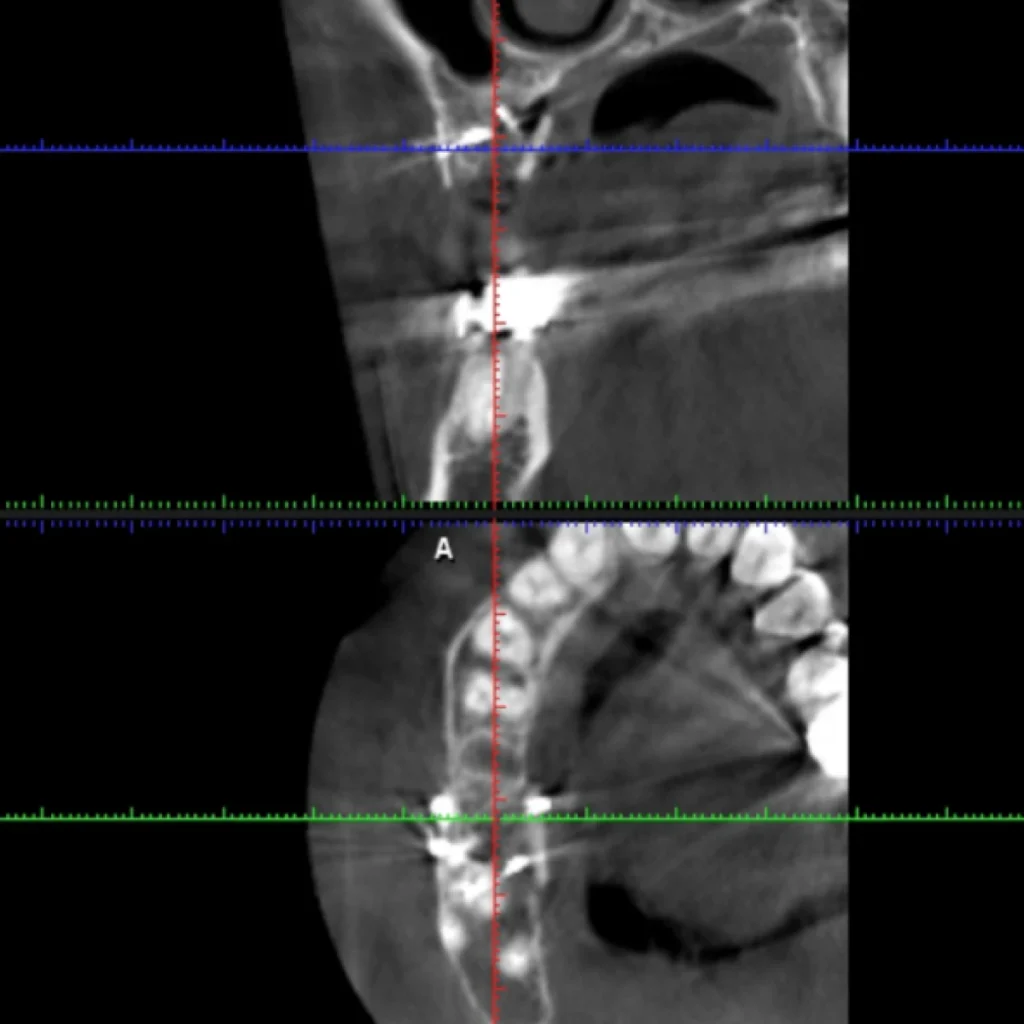

Un cone beam (équivalent d’un scanner) est réalisé sur place afin de valider le diagnostique et de vous proposer le traitement adapté à votre situation. Certaines font intervenir des biomatériaux (os de banque d’origine humaine ou animale; os de synthèse; os autogène prélevé directement dans votre bouche lors de l’intervention).

- Le scanner réalisé au cabinet met en évidence un défaut osseux majeur nécessitant une greffe osseuse complexe pour réhabiliter la zone par 2 implants.